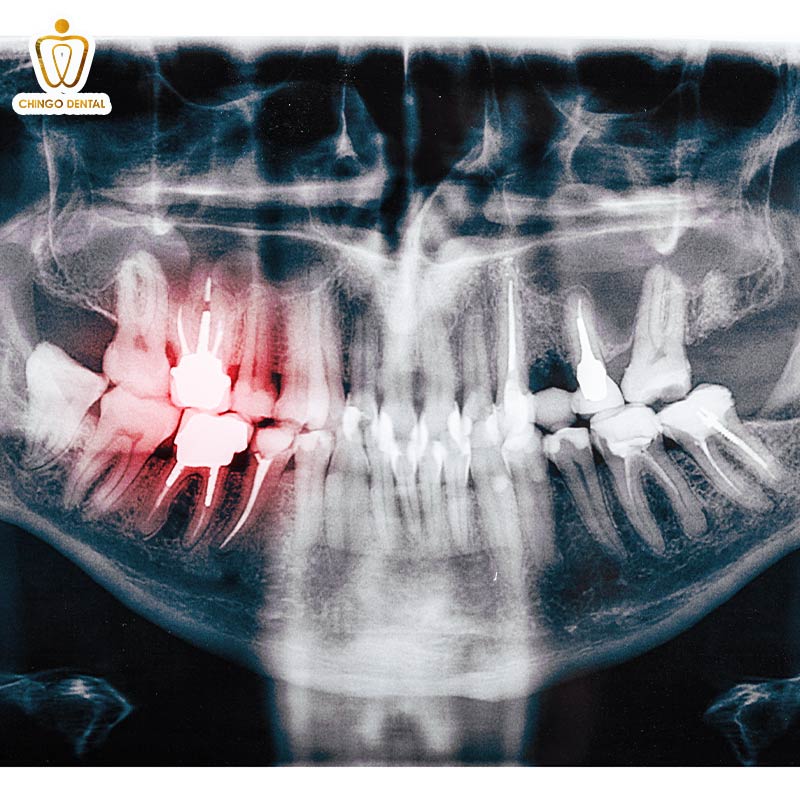

Phim Panorama: Bức tranh toàn cảnh về nụ cười

Nếu phim cận chóp là ảnh chân dung, thì Panorama chính là một bức ảnh “Check – in toàn cảnh”. Thay vì chỉ tập trung vào một chiếc răng, máy chụp X-quang răng sẽ quay một vòng quanh đầu bạn. Để ghi lại hình ảnh của cả hai hàm, các xoang vùng mặt và khớp thái dương hàm.

Phim chụp X-quang răng toàn cảnh là “người bạn đồng hành” không thể thiếu khi bạn muốn khám tổng quát. Hoặc tìm kiếm những chiếc răng khôn đang mọc lệch thông qua chụp phim răng. Giúp bác sĩ có cái nhìn bao quát về tình trạng sức khỏe răng miệng của bạn.